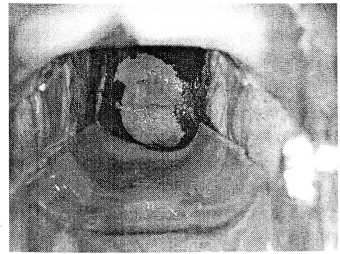

Для более точной диагностики мы рекомендуем начинать осмотр женщины, пришедшей на кольпоскопию, с вульвоскопии. При осмотре малых половых губ вульвы можно выявить мелкие разрастания в складках слизистой (рис. 3), что может быть аргументом для обследования на ВПЧ.

Рис. 3. Единичные кондиломы и папилломы вульвы

На рис. 3 при вульвоскопии в складке слизистой между вульвой и правой малой половой губой выявляется мелкая единичная кондилома. Характерным микроскопическим признаком кондиломатозного разрастания является повышенный сосудистый рисунок в виде «кроны дерева». Под пальцем визуализируется еще одна мелкая кондилома на гребне нижней трети правой малой половой губы.